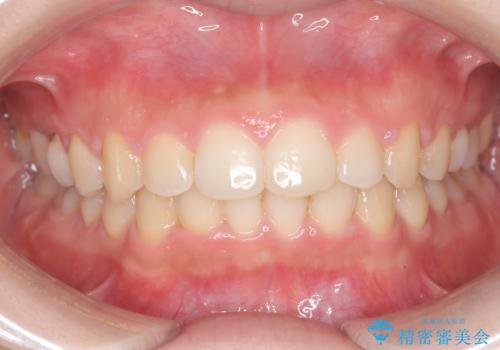

【ワイヤー矯正】前歯のがたがたをなおしたい

- 治療期間

- 1年

- 前歯のがたがたを主訴に来院されました。

叢生量も軽度なため短期間で治療を行っています。